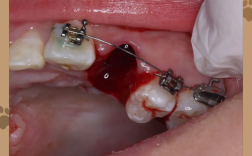

当牙齿拥挤度较大(通常拥挤度超过8mm)时,仅通过少量扩展牙弓或移动牙齿,难以完全排齐,强行在不拔牙的情况下排齐牙齿,可能导致牙齿唇倾(“龅牙”)、牙龈萎缩、牙根吸收等问题,孩子上前牙严重拥挤、扭转,甚至部分牙齿完全重叠在牙弓内,此时拔除1-2颗前磨牙,能为拥挤的牙齿提供“移动通道”,使其排列到正常位置。